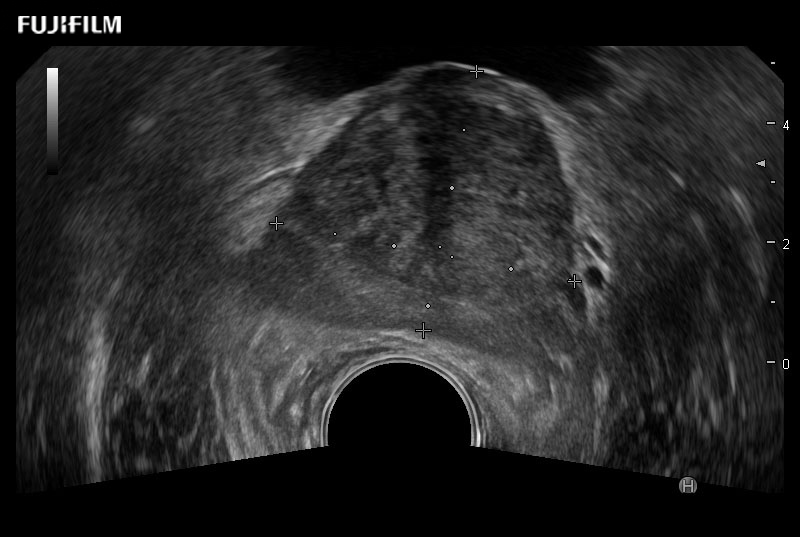

Exclusive 200° FOV end-fire prostate biopsy transducer.

Provides real-time imaging of both the sagittal and transverse planes